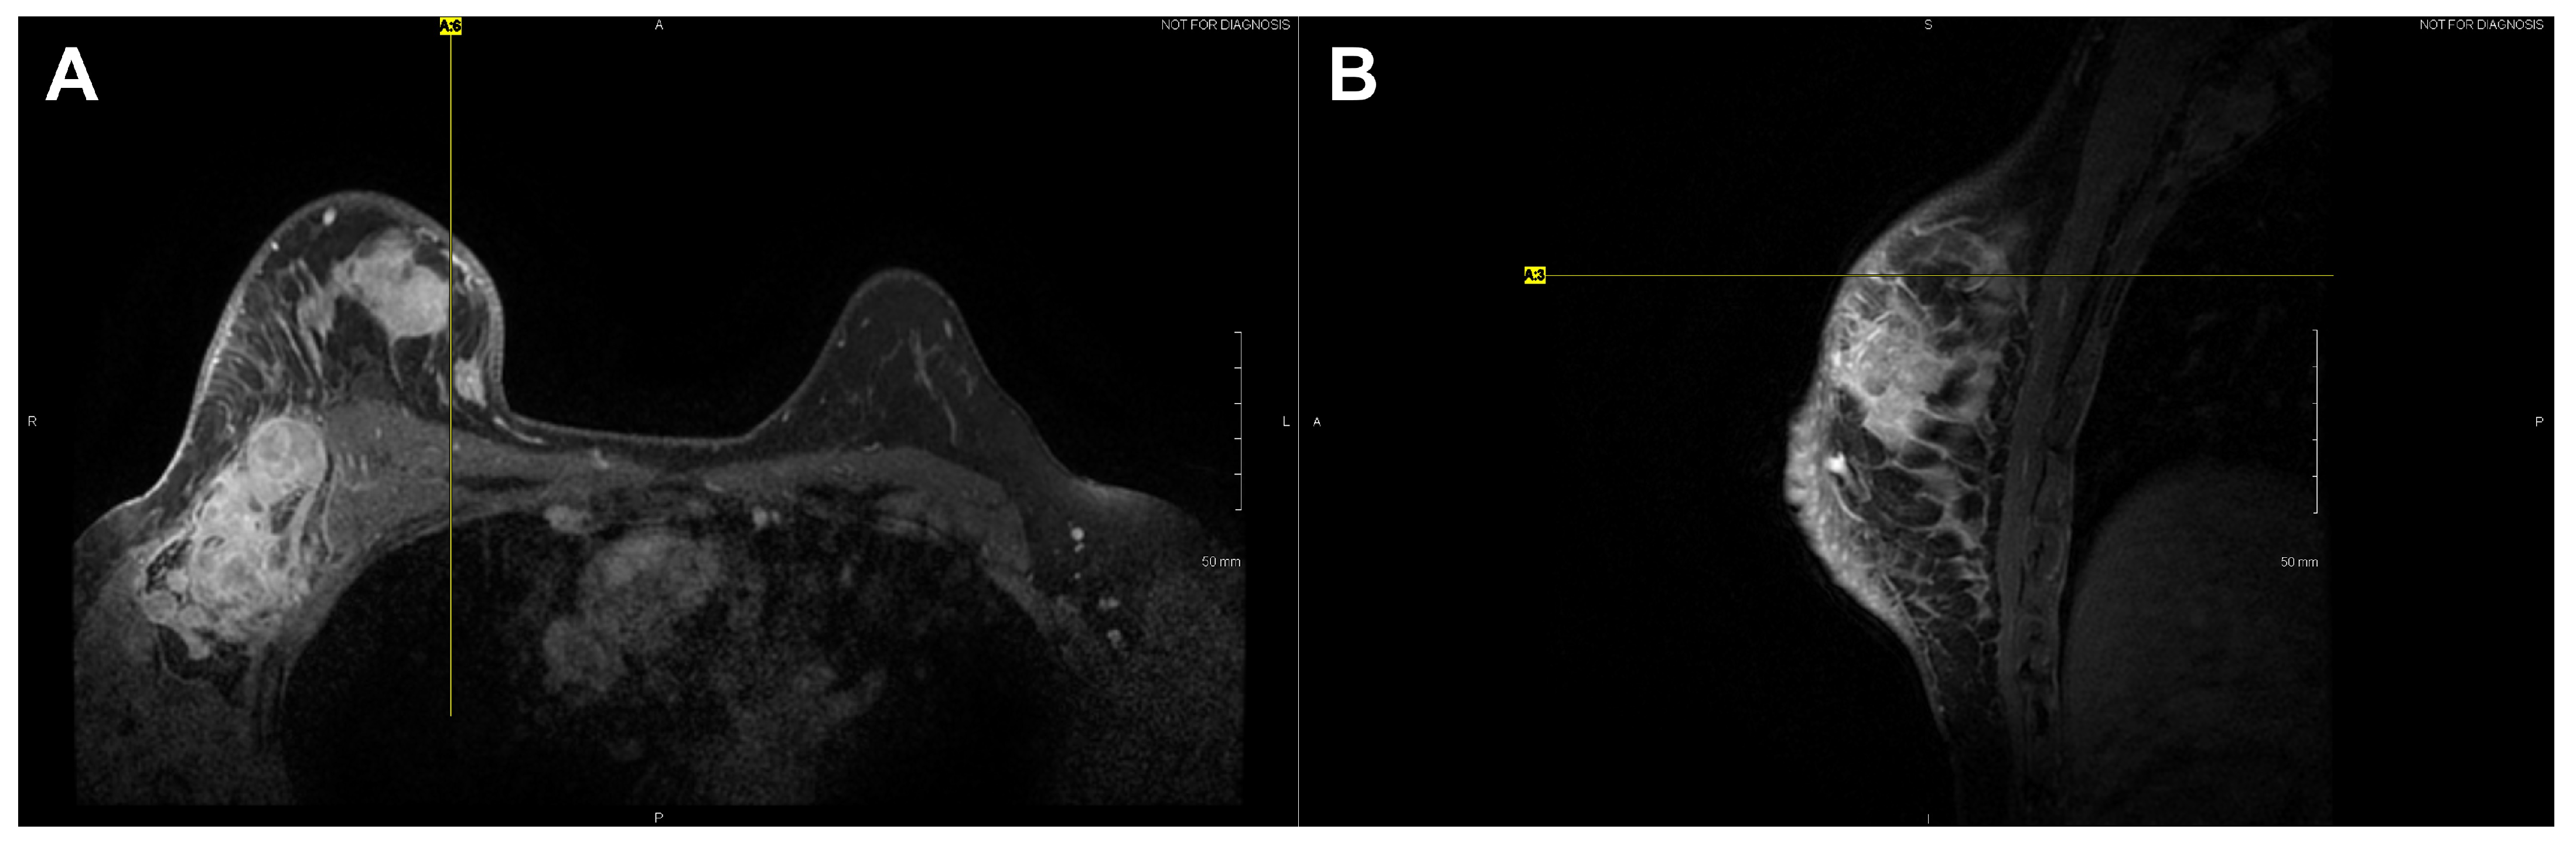

| 04 * | Malignant | Left | Phyllodes | High | 17.5 cm (mammo) | Mass occupied entire breast | – | – | Non-mammary origin (stromal cancer) |

| 09 | Malignant | Left | IDC | 3 | 3.6 cm (US) | 12:00, 2 cm, from nipple (dominant mass) UOQ, 1:00, 2 cm from nipple (satellite mass) | ER+, PR+, HER2/neu+ | 2b | – |

| 10 | Malignant | Right | IDC | 3 | 4.4 cm (US); 5.2 cm (MR) | UIQ, 1:00, 2 cm from nipple (dominant mass) UIQ, 2:00, 8 cm from nipple (satellite mass) | ER−, PR−, HER2/neu− | 3b (inflammatory) | Triple negative |

| 11 | Malignant | Left | IDC (NOS) | 3 | 8 cm (mammo) | UOQ, 2:00, 4 cm from nipple (dominant mass) UOQ, 2:00; UIQ, 10:00 (satellite masses) | ER−, PR−, HER2/neu− | 2b | Triple negative; multiple adjacent satellite masses |